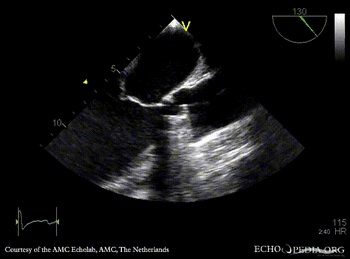

Thrombus of prosthetic aortic valve

TEE: thrombus of prosthetic aortic valve TEE: severe aortic regirgitation